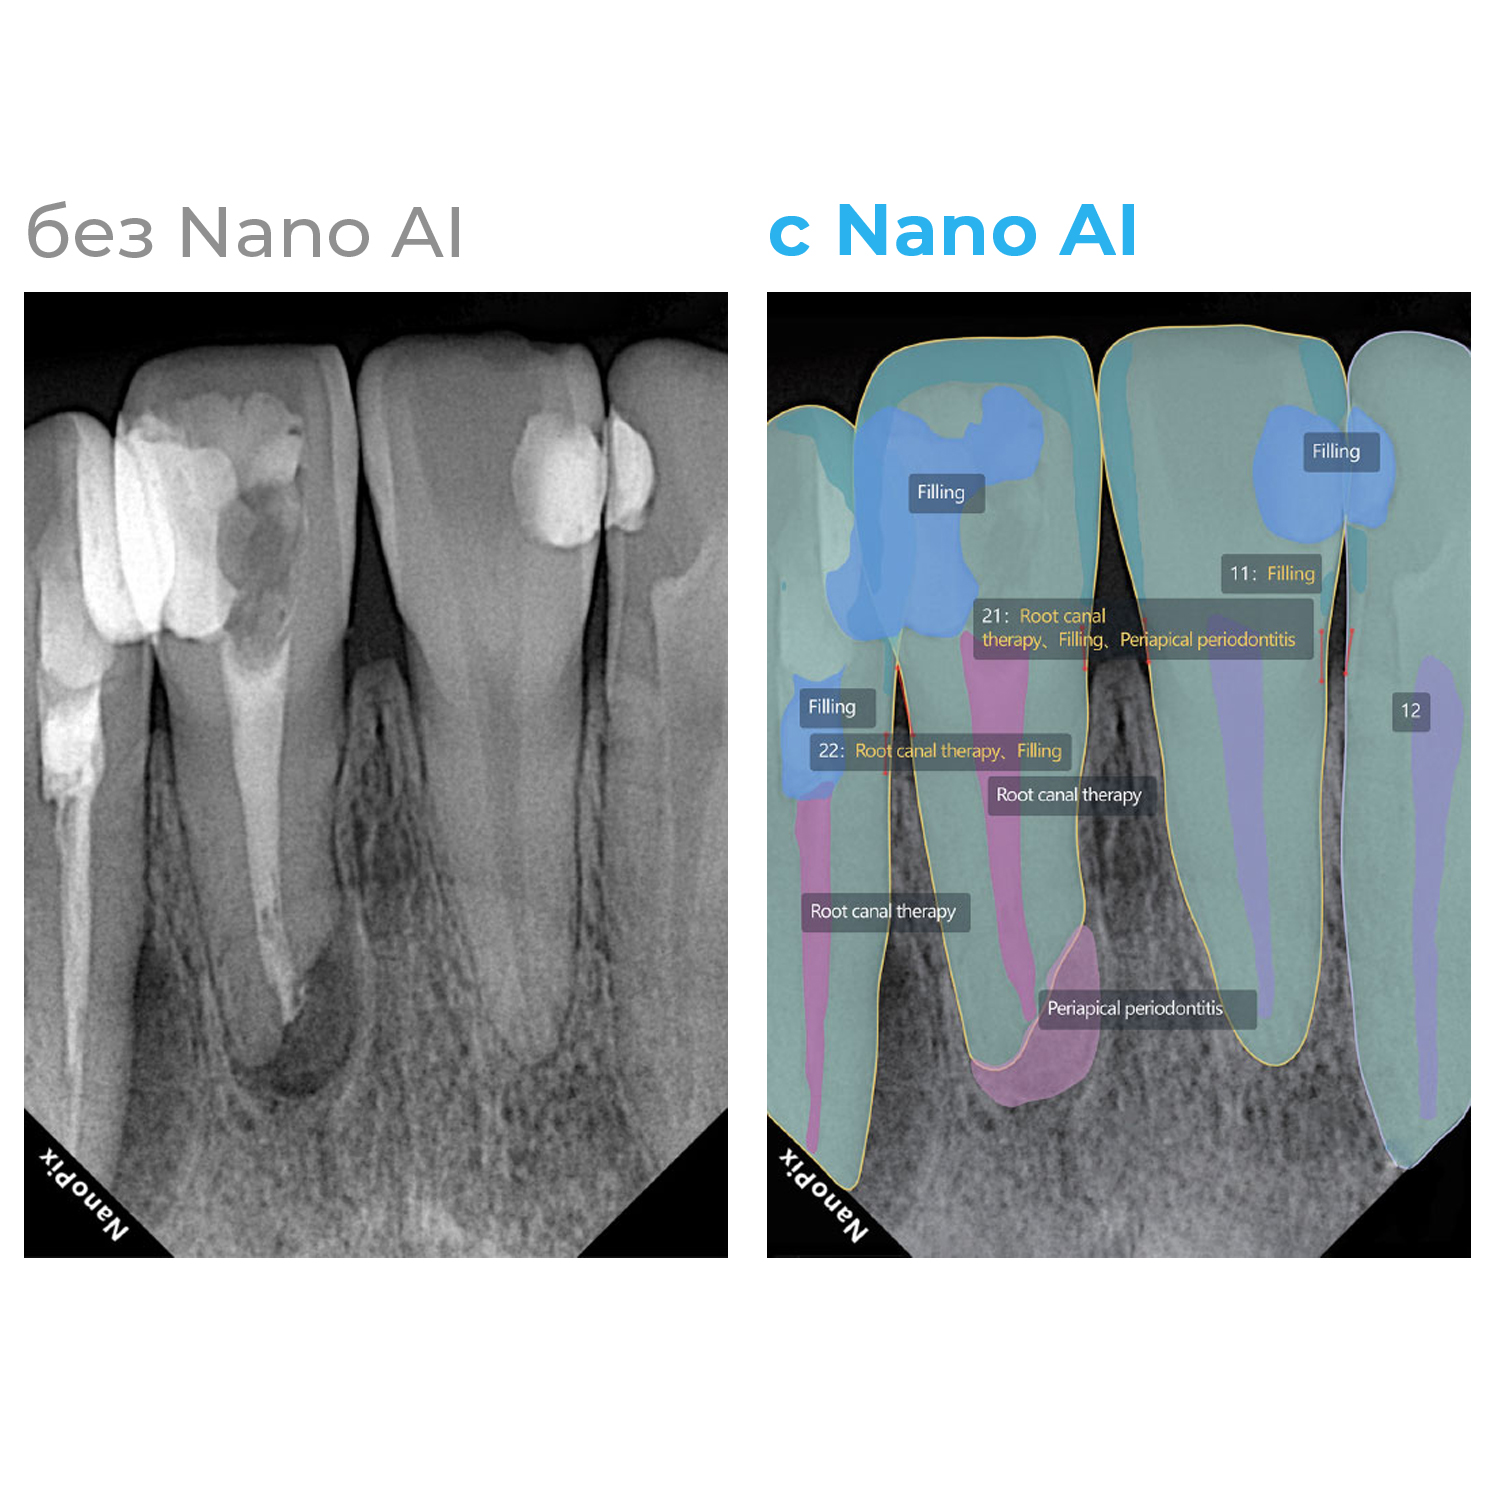

Прибор оснащён высокочувствительным сенсором, с помощью которого устройство фиксирует и передаёт изображение в цифровом виде на компьютер. Принцип работы заключается в следующем: цифровой радиовизиограф размещается в ротовой полости пациента за зубами. С щёчной стороны дентальный рентгеновский аппарат выпускает в направлении радиовизиографа рентгеновские лучи. Лучи, проходя через ткани зуба, фиксируются на радиовизиографе, и полученная информация отображается на экране компьютера. Уникальная технология искусственного интеллекта Nano AI распознаёт зубные патологии, выделяя их цветом и предлагая возможные способы лечения.